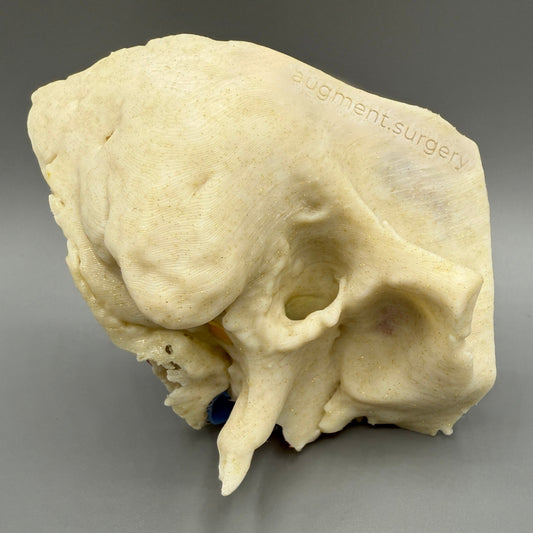

Plant-based surgical simulators made in the U.S.A.

Dissect each one to learn human temporal bone anatomy, hearing and vestibular systems.

Delta-Left OpenEar 3D Temporal Bones

Regular price $74.00 USDRegular priceUnit price per -

Delta-Right OpenEar 3D Temporal Bones

Regular price $74.00 USDRegular priceUnit price per -